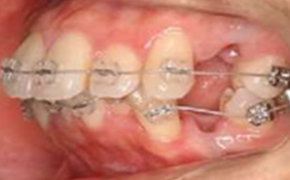

マウスピース矯正前

マウスピース矯正を行う前に準備矯正が必要な場合があります。

「第一小臼歯を抜歯後、犬歯(糸切り歯)だけを引いておく」など、ワイヤーの力を使い、動きにくい歯を動きやすい位置まで、あらかじめ移動させておく矯正です。